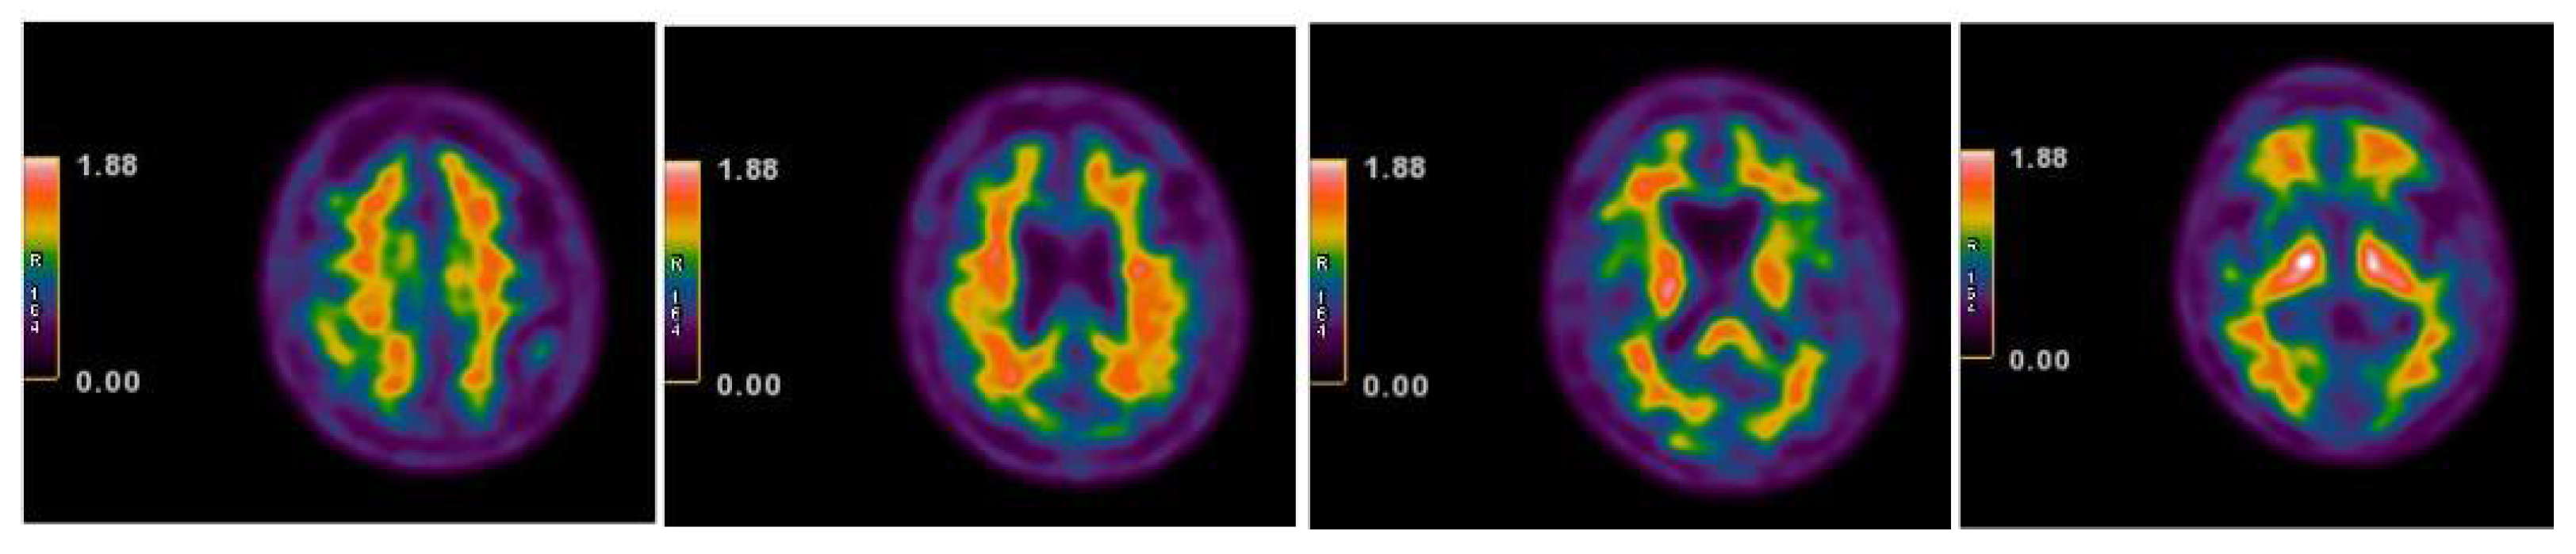

| 2013 | FDG-PET | Hypometabolism in the right and left premotor cortex |

| 2015 | Neurological assessment FDG-PET | Mild isolated motor speech disorder hypometabolism; more extensive involving left temporal gyrus, frontal gyrus bilaterally, cingulate, caudate, and thalamus bilaterally |

| 2017 | Neurological assessment Neuropsychological assessment (WAIS-IV) Speech therapist assessment Amyloid PET | Mild isolated motor speech disorder No abnormal β-amyloid deposits |